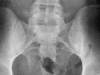

Low back pain